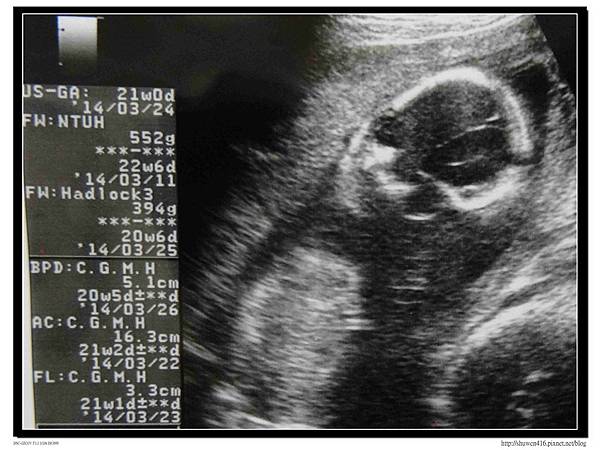

本次產檢安寶寶長大不少,目前重量552g,醫生給了一張正面的超音波照片,安寶寶的五官和四肢都很健康,從超音波看來是個頭好壯壯的寶寶,因媽咪的羊水量很ok,所以安寶寶在子宮裡活動的很開心,還不忘透過超音波和安安姊姊揮手打招呼,讓安安也不停揮手回應,但最近的胎動強度慢慢增加,有時還會將媽咪肚皮踢到有點疼。